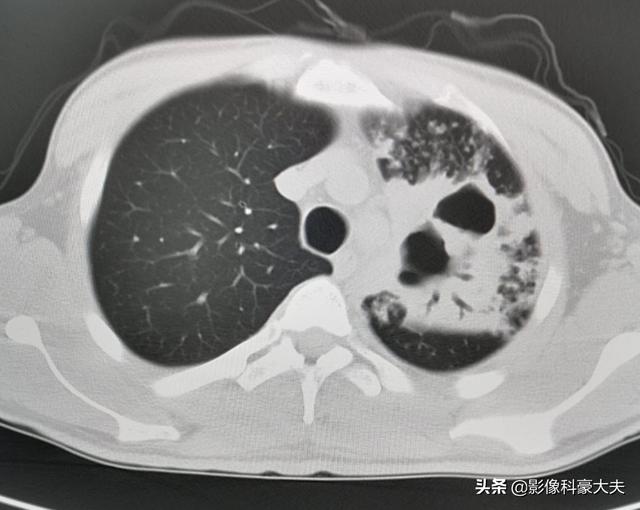

Ce patient, âgé d'un peu plus de 30 ans, avait une glycémie supérieure à 20. Il souffrait d'une infection secondaire de la tuberculose avec destruction massive du tissu pulmonaire du côté gauche et formation de multiples grandes cavités, et crachait du sang.

Les diabétiques dont la fonction immunitaire est réduite sont sensibles aux infections telles que Staphylococcus aureus, Aspergillus, Mycobacterium tuberculosis, Klebsiella pneumoniae, etc. Certaines infections progressent rapidement et peuvent être fatales en peu de temps.

Ce chap était OK, et après un an de traitement systématique, les lésions ont été significativement résorbées.